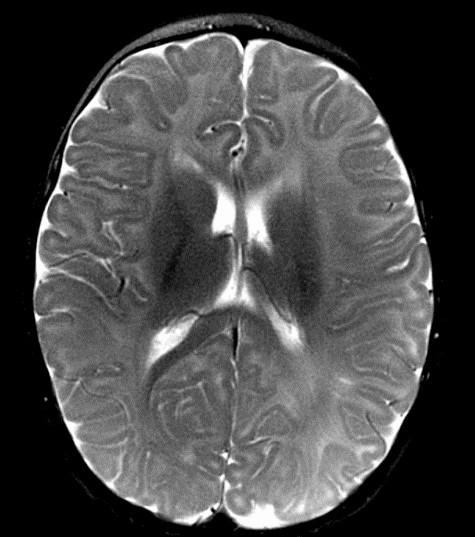

Run the Rim:

Start at noon and evaluate the cortex clockwise, should be 2-33 mm thick.

Sweep the Midline: What parts are missing?

Run the Rim…where is the cortex “too thick?”

“Missing”=disorganized rostrum, genu, anterior body of the corpus callosum Cortex of the anterior medial frontal lobes “too thick” with fused grey matter across the anterior midline where the “genu” should be.